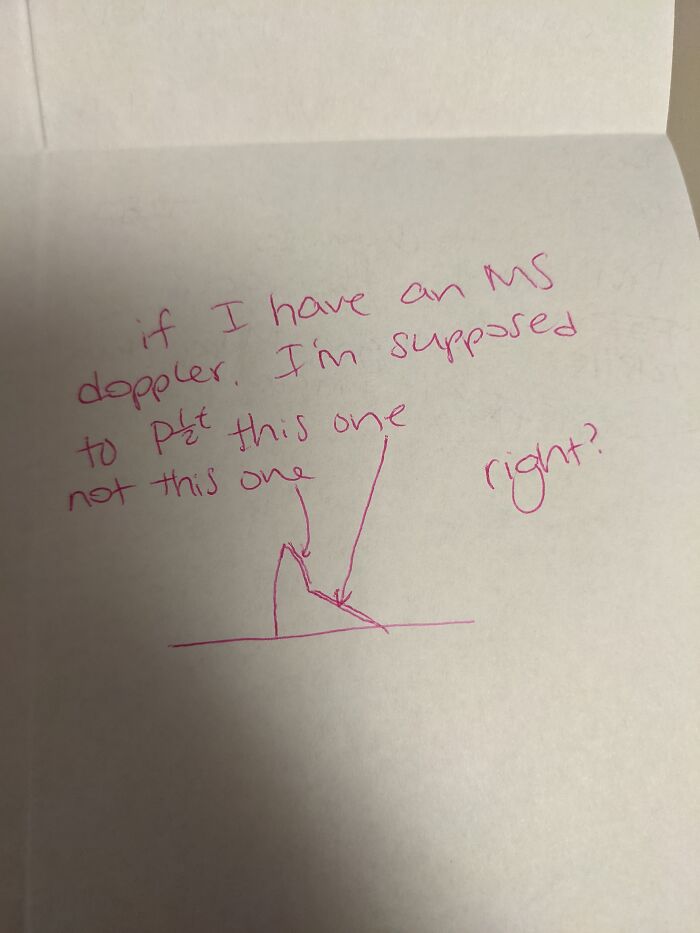

Everybody On Here Is Like "Here's My Precious Fur Baby!!" And I'm Just Looking At My 5th Image Of A Work Question I Texted To My Boss..